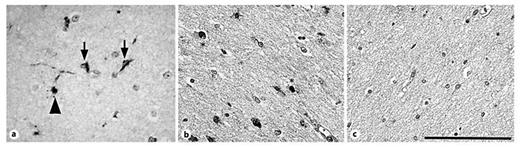

In the diffusely gliotic component of PVL surrounding and distant from the focal necrosis, we found 12/15-LOX-positive cells in the white matter. These cells had the morphological appearance of microglia characterized by bipolar thick processes [44] (fig. 3a), or of OLs characterized by a central, dark, round, and small nucleus and often with a 12/15-LOX-stained process extending towards an axon (fig. 3a). We also observed scattered cells of unknown type with 12/15-LOX-positive nuclei in the white matter of PVL cases (fig. 3b). The 12/15-LOX expression appeared qualitatively increased in the white matter in PVL (fig. 3a, b) compared to controls (fig. 3c). To confirm this visual difference, we used a semiquantitative scoring system of 0-3 and found a significant increase (p = 0.014) in the density of 12/15-LOX-expressing cells in PVL (score of 1.17 ± 0.15 cells/HPF) compared to controls (score of 0.48 ± 0.21 cells/HPF) during the second half of gestation (fig. 4). Examination of the number of cases scored 0-3 revealed a larger number of control cases with scores of 0 and 0.5 (n = 8 out of 10; 80%) relative to the PVL cases which showed an increased number of cases with scores of 1 and 2 (n = 15 out of 19; 79%). ANCOVA showed no effect of postmortem interval (p = 0.15) in a model that controlled for diagnosis. Of note, there was no significant expression of 12/15-LOX in the cerebral cortex of PVL cases (data not shown).

12/15-LOX expression in the diffusely gliotic lesion of PVL. All images are shown at a magnification of ×40, scale bar = 100 μm. a 12/15-LOX is expressed in glial cells of the diffusely gliotic lesion in a PVL case at 40 PC weeks. Arrows indicate cells with the morphological appearance of microglia. The arrowhead indicates a cell with the appearance of an OL. b 12/15-LOX expression is detected in scattered nuclei (asterisks) of cells in the gliotic white matter of a PVL case at 39 PC weeks. c There is no detectable expression of 12/15-LOX in the white matter of a control case at 40 PC weeks.